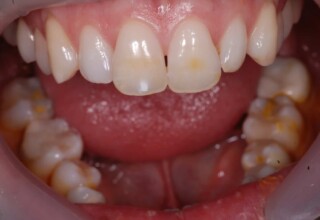

Δύσχρωμα απονευρωμένα δόντια

Μια ιδιαίτερη περίπτωση δύσχρωμων απονευρωμένων δοντιών που ο κεντρικός είχε βλάβη από εξωτερική απορρόφηση. Έγινε καθαρισμός του κεντρικού από την βλάβη και επειδή δεν μπορούσε να λευκανθεί λόγω της επαφής με τα ούλα, σφραγίστηκε σε πρώτη φάση, μετά λευκάνθηκε και στο τέλος έγινε η τελική αποκατάσταση.